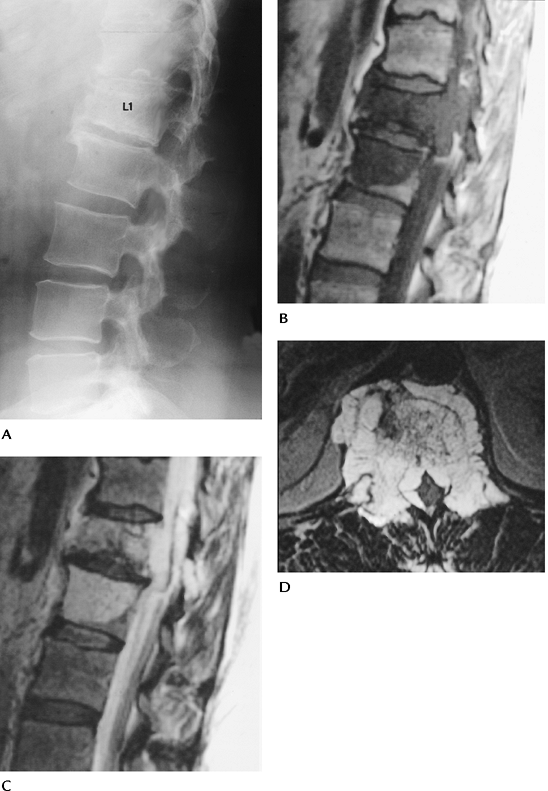

FIGURE 3-66 Spinal chordoma. (A)

Lateral radiograph shows sclerosis and compression of L1 (15% of chordomas involve the spine, 50% involve the sacrum, 30% to 70% may calcify). Sagittal T1-weighted (B) and T2-weighted (C) and axial contrast-enhanced image (D) demonstrate extension of tumor from L1 to L2 with extension around the dural sac. |